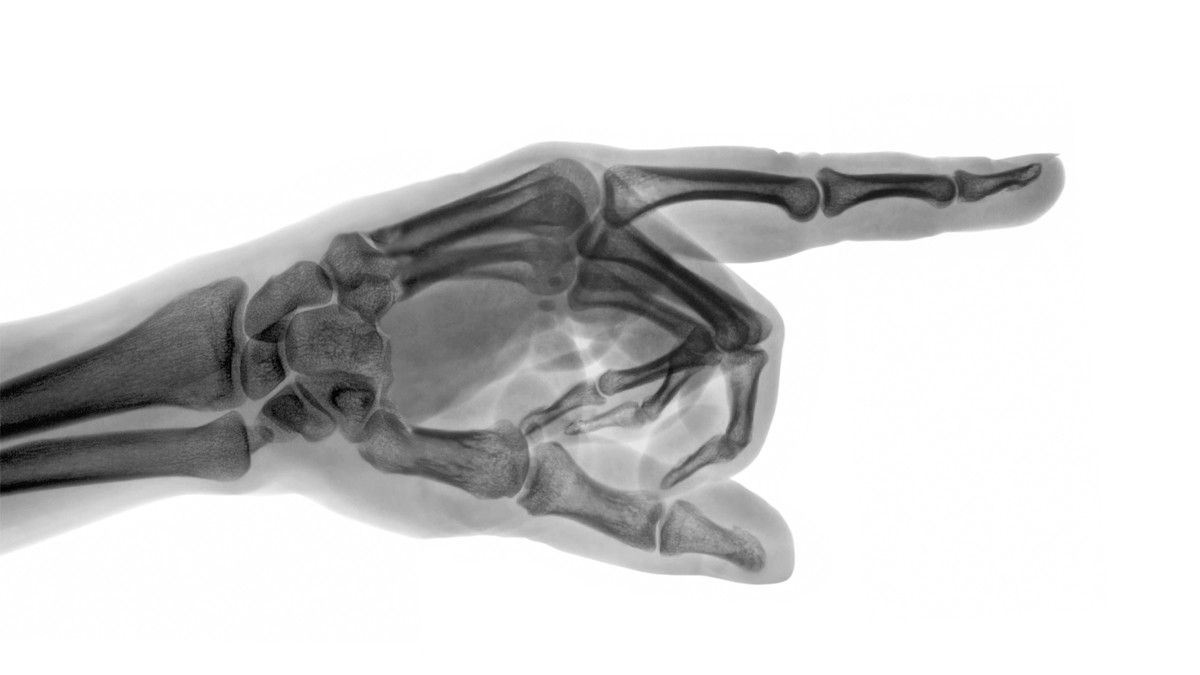

Menurut dr. Devia Irine Putri, untuk mengetahui atau mendiagnosis jenis kanker tulang, ada beberapa tahapan yang perlu dilakukan oleh dokter.

“Selain dari wawancara medis dan pemeriksaan fisik, biasanya akan didukung dengan pemeriksaan lain, seperti tes pencitraan, rontgen, CT scan, MRI dan juga melakukan biopsi,” jelas dr. Devia.